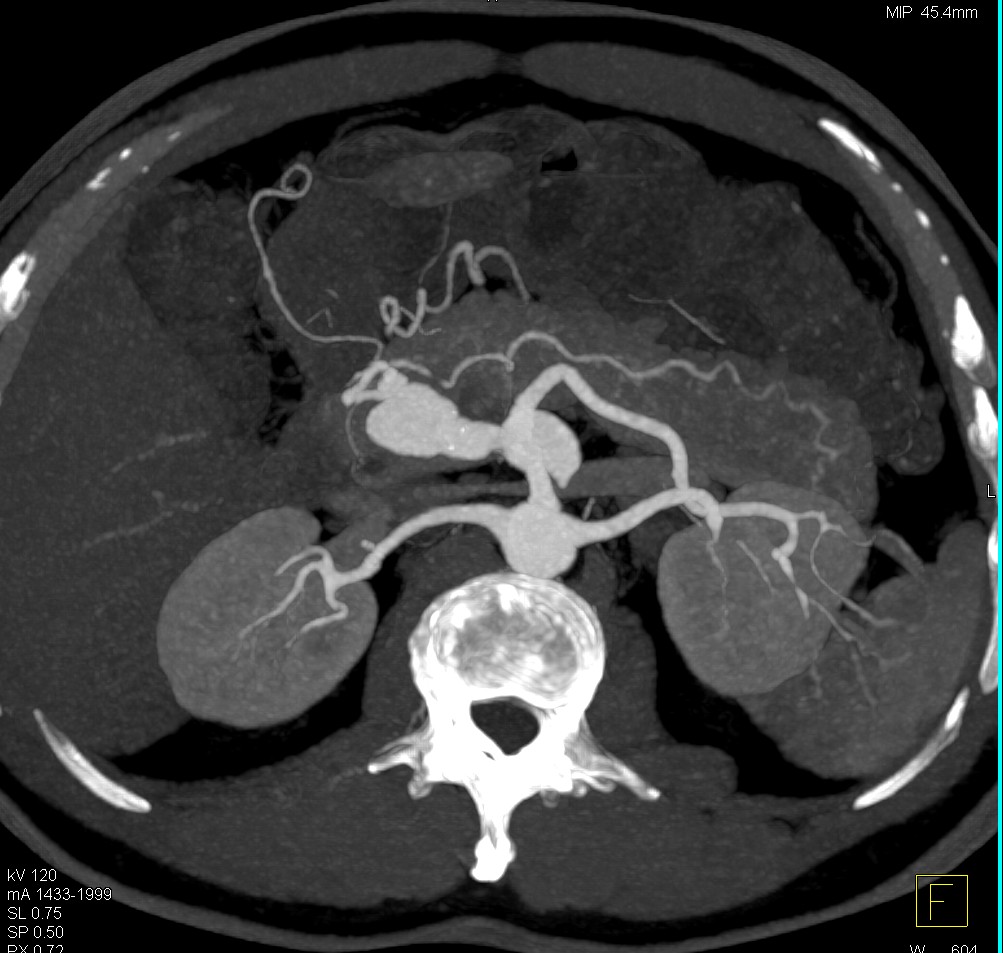

Hepatic Artery Aneurysm